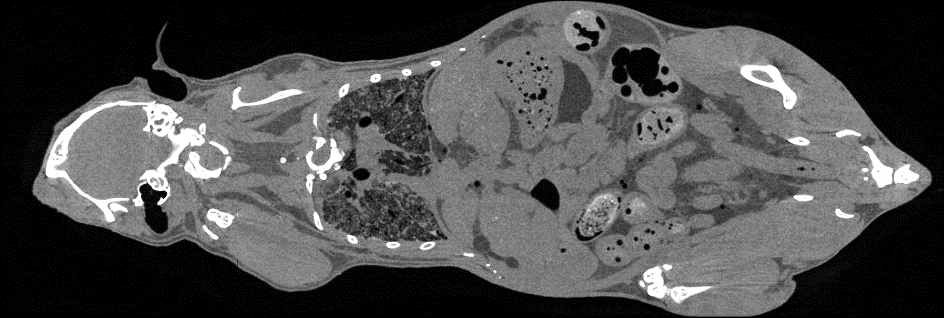

随着临床前研究向着活体成像、高分辨成像、多模成像等应用发展,传统的显微CT技术已无法满足生命科学领域的研究需求。近年来,基于光子计数探测器的能谱CT已成为当前CT新技术的重要发展方向,高分辨X射线能谱CT成像技术正在快速发展。在中科院装备研制等项目的支持下,项目团队研发出国际首台小动物活体能谱显微CT设备,通过以微米级分辨及多能谱图像再现动物体内的各器官组织的精细结构,实现动物实验从离体到活体、从黑白到彩色的进步,为生物医学研究提供更为先进的实验手段和科学仪器。

小动物活体能谱显微CT已经为国内科研院所、高校和医院完成了一批高质量动物实验,未来能够为口腔疾病研究、骨研究、肿瘤研究、心血管疾病研究、生物材料研究和开发、新药开发等多个领域提供先进的研究工具。

小动物活体能谱显微CT设备

鼠全身成像